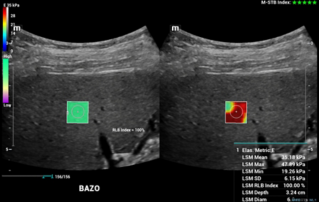

Comprehensive overview of granulosa theca cell tumors of the ovary, covering epidemiology, clinical presentation, diagnosis, treatment options, and prognosis for both adult and juvenile types.